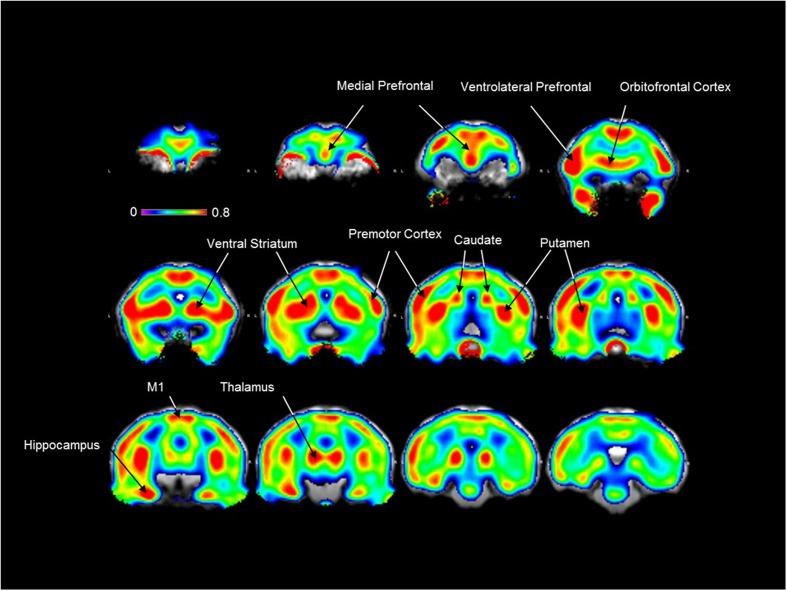

Brain serotonin-6 receptor (5-HTR) is the one of the most recently identified serotonin receptors. Accumulating evidence suggests that it is a potent therapeutic target for psychiatric and neurological diseases. Since [F]2FNQ1P was recently proposed as the first fluorinated positron emission tomography (PET) radioligand for this receptor, the objective of the present study was to demonstrate its suitability for 5-HTR neuroimaging in primates. [F]2FNQ1P was characterized by autoradiography and PET imaging in cynomolgus monkeys. Following PET imaging, tracer binding indices were computed using the simplified reference tissue model and Logan graphical model, with cerebellum as reference region. The tracer binding reproducibility was assessed by test-retest in five animals. Finally, specificity was assessed by pre-injection of a 5-HTR antagonist, SB258585. results showed wide cerebral distribution of the tracer with specificity toward 5-HTRs as binding was effectively displaced by SB258585. brain penetration was good with reproducible distribution at cortical and subcortical levels. The automated method gave the best spatial normalization. The Logan graphical model showed the best tracer binding indices, giving the highest magnitude, lowest standard deviation and best reproducibility and robustness. Finally, 5-HTR antagonist pre-injection significantly decreased [F]2FNQ1P binding mainly in the striatum and sensorimotor cortex. Taken together, these preclinical results show that [F]2FNQ1P is a good candidate to address 5-HT6 receptors in clinical studies.

脑血清素-6受体(5-HTR)是最近发现的血清素受体之一。越来越多的证据表明,它是治疗精神疾病和神经疾病的有效靶点。由于[F]2FNQ1P最近被提议作为该受体的首个氟化正电子发射断层扫描(PET)放射性配体,本研究的目的是证明其适用于灵长类动物的5-HTR神经成像。通过食蟹猴的放射自显影和PET成像对[F]2FNQ1P进行了表征。PET成像后,使用简化参考组织模型和洛根图形模型,以小脑为参考区域计算示踪剂结合指数。通过对五只动物进行重测评估示踪剂结合的重现性。最后,通过预先注射5-HTR拮抗剂SB258585评估特异性。结果显示,该示踪剂在脑内分布广泛,对5-HTR具有特异性,因为SB258585有效地取代了结合。脑渗透性良好,在皮质和皮质下水平分布具有可重复性。自动方法给出了最佳的空间归一化。洛根图形模型显示了最佳的示踪剂结合指数,幅度最高、标准差最低、重现性和稳健性最佳。最后,预先注射5-HTR拮抗剂主要使纹状体和感觉运动皮层的[F]2FNQ1P结合显著降低。综上所述,这些临床前结果表明,[F]2FNQ1P是临床研究中针对5-HT6受体的良好候选物。